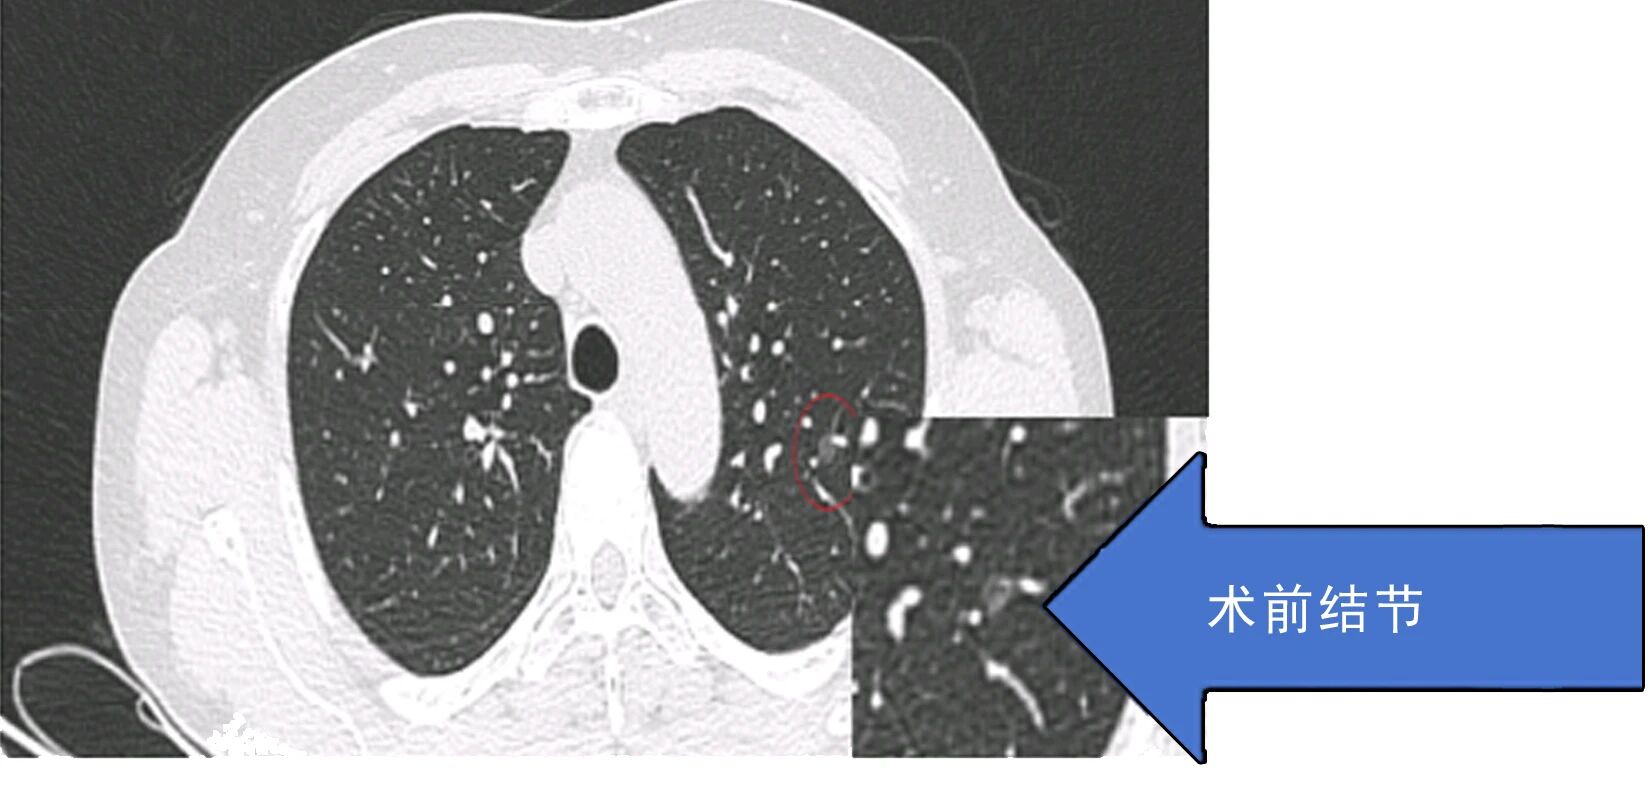

患者因肺结节就诊后,术前检查提示传统手术可能造成较大肺功能损伤,患者及家属因此产生明显焦虑情绪。胸外科团队综合评估病情后,决定采用微波消融技术施治。手术依托CT实时导航技术,将消融针精准送达结节部位,误差控制在3毫米以内,仅通过一个针孔创口完成操作,单次消融过程耗时5-10分钟,患者3天内出院,健康肺组织功能得以保留。

据悉,微波消融技术虽有微创优势,但不能替代传统根治性手术——对于可耐受手术的早期肺癌患者,手术切除仍是临床金标准。该技术更适用于直径≤3cm的孤立性周围型高危小结节、数量≤5个的多发结节患者,以及心肺功能差、无法耐受手术的高龄高危人群,同时可作为拒绝手术者、术后复发或残留结节患者的辅助治疗方案。 技术突破背后,离不开医院完善的硬件支撑与多学科协作机制。术前需经多学科团队(MDT)严格评估,确保患者符合适应症要求。胸心外科始终坚持肺结节治疗“量体裁衣”原则,强调早发现、早干预与规律随访的重要性,未来将进一步探索微创与微波技术的联合应用模式,持续提升肺结节诊疗精准度与患者就医体验。